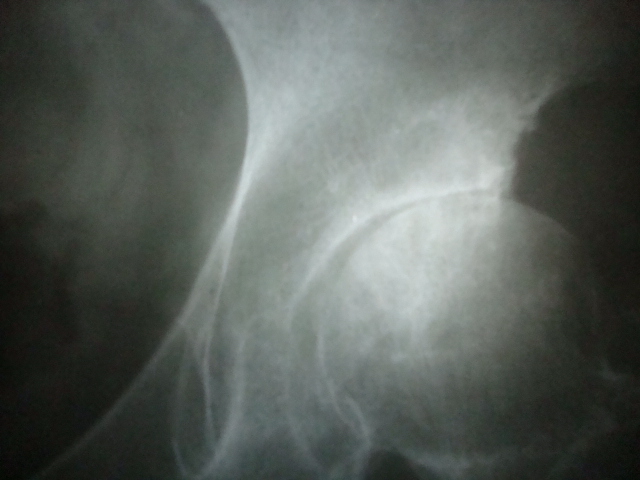

患者女58岁左腿跛行数月。

左侧髋关节间隙明显变窄,髋臼上缘硬化,左股骨头骨质未见明显异常,首先考虑左侧髋关节退变,可结合ct或mri检查看有否股骨头坏死。

左髋关节间隙明显变窄,髋臼上缘硬化。左股骨头可见斑点状密度减低区。双髋臼稍扁平。考虑双髋关节发育不良导致退变。建议mri排除左股骨头坏死

首先考虑股骨头缺血坏死继发骨性关节炎终末期改变。

与退变鉴别点在于坏死发病早,股骨颈变短增粗,股骨头及髋臼畸形明显。

左侧髋关节间隙变窄,左股骨头内骨质密度不均,考虑缺血型坏死可能性大,建议ct检查,髋臼边缘未见骨质增生征,不支持关节炎。

不支持先有股骨头无菌坏死伴发退变:如果是股骨头坏死,关节间隙明显变窄了,那么就该4期以上了,显然股骨头改变不重。

左髋关节发育不良所致退行性变,股骨头缺血性坏死早期少有关节间隙的改变